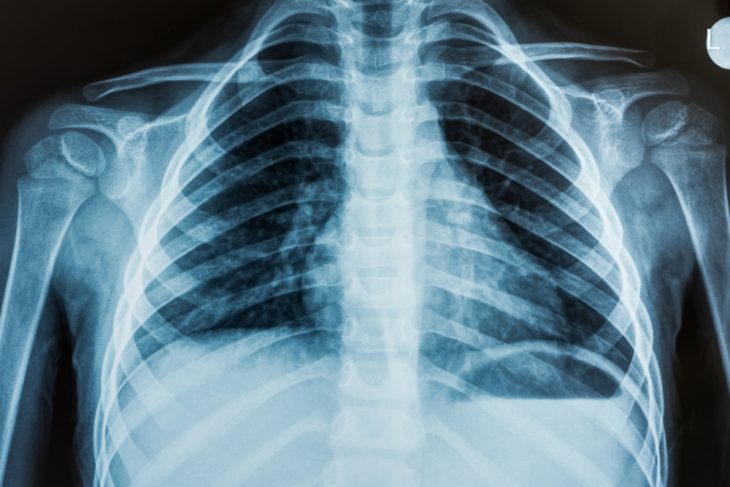

Рентгенография грудной клетки выполняется с целью исследования легких, сердца и грудной стенки. Это неинвазивная методика, при которой тело пациента подвергают воздействию ионизирующего излучения. Результатом процедуры являются пленочные снимки или цифровые изображения.

В основе исследования лежит различие в способности органов и тканей поглощать рентгеновские лучи. Известно, что чем плотнее анатомическая структура, тем сильнее она «впитывает» в себя радиацию. Так, например, ребра в процессе рентгенографии поглощают практически всю дозу пропускаемого через них излучения, в то время как легкие – не более 5 %. В итоге костные ткани на снимках выглядят практически белыми, а воздушные полости – черными.

Интерпретацией полученных изображений занимается врач-рентгенолог. Он оценивает структуру костей и мягких тканей грудной клетки. Имеют значение:

- расположение верхушек легких,

- прозрачность легочной ткани,

- форма и размеры теней органов средостения,

- наличие дополнительных затемнений (очагов и фокусов) на проекции легких.

В числе патологических изменений могут быть обнаружены гранулемы бронхов, экссудат или воздух в плевральной полости, кисты легких и др.

Результаты диагностики рентгенолог оформляет в виде заключения, которое вместе с пленочными снимками или цифровыми изображениями передает лечащему врачу.